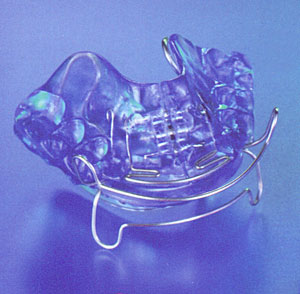

| mit Aktivatoren zur Bissverschiebung und Bisshebung in der Wachstumsphase |

Aktivator *

| mit aktiven Platten zur Streckung, Verkürzung und Verbreiterung der Zahnbögen |

Aktive Platte *